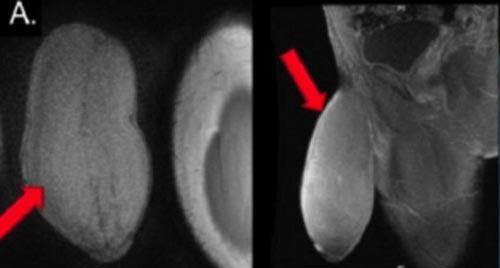

| Ảnh chụp X-quang cho thấy dương vật của bệnh nam 17 tuổi phát triển lớn dị thường, gây nhiều bất tiện và khó chịu cho khổ chủ. |

Các bác sĩ phẫu thuật cho chàng trai thực sự bị sốc khi cậu tìm đến chỗ họ than phiền về "súng ống quá khủng". Khi ở trạng thái ỉu xìu, nó có số đo chiều dài gần 17,8 cm với chu vi tới 25,4 cm, tức là tương đương kích cỡ một quả bưởi. Các chuyên gia phẫu thuật thậm chí mô tả "cậu nhỏ" đặc biệt này có hình dạng của một quả bóng bầu dục.